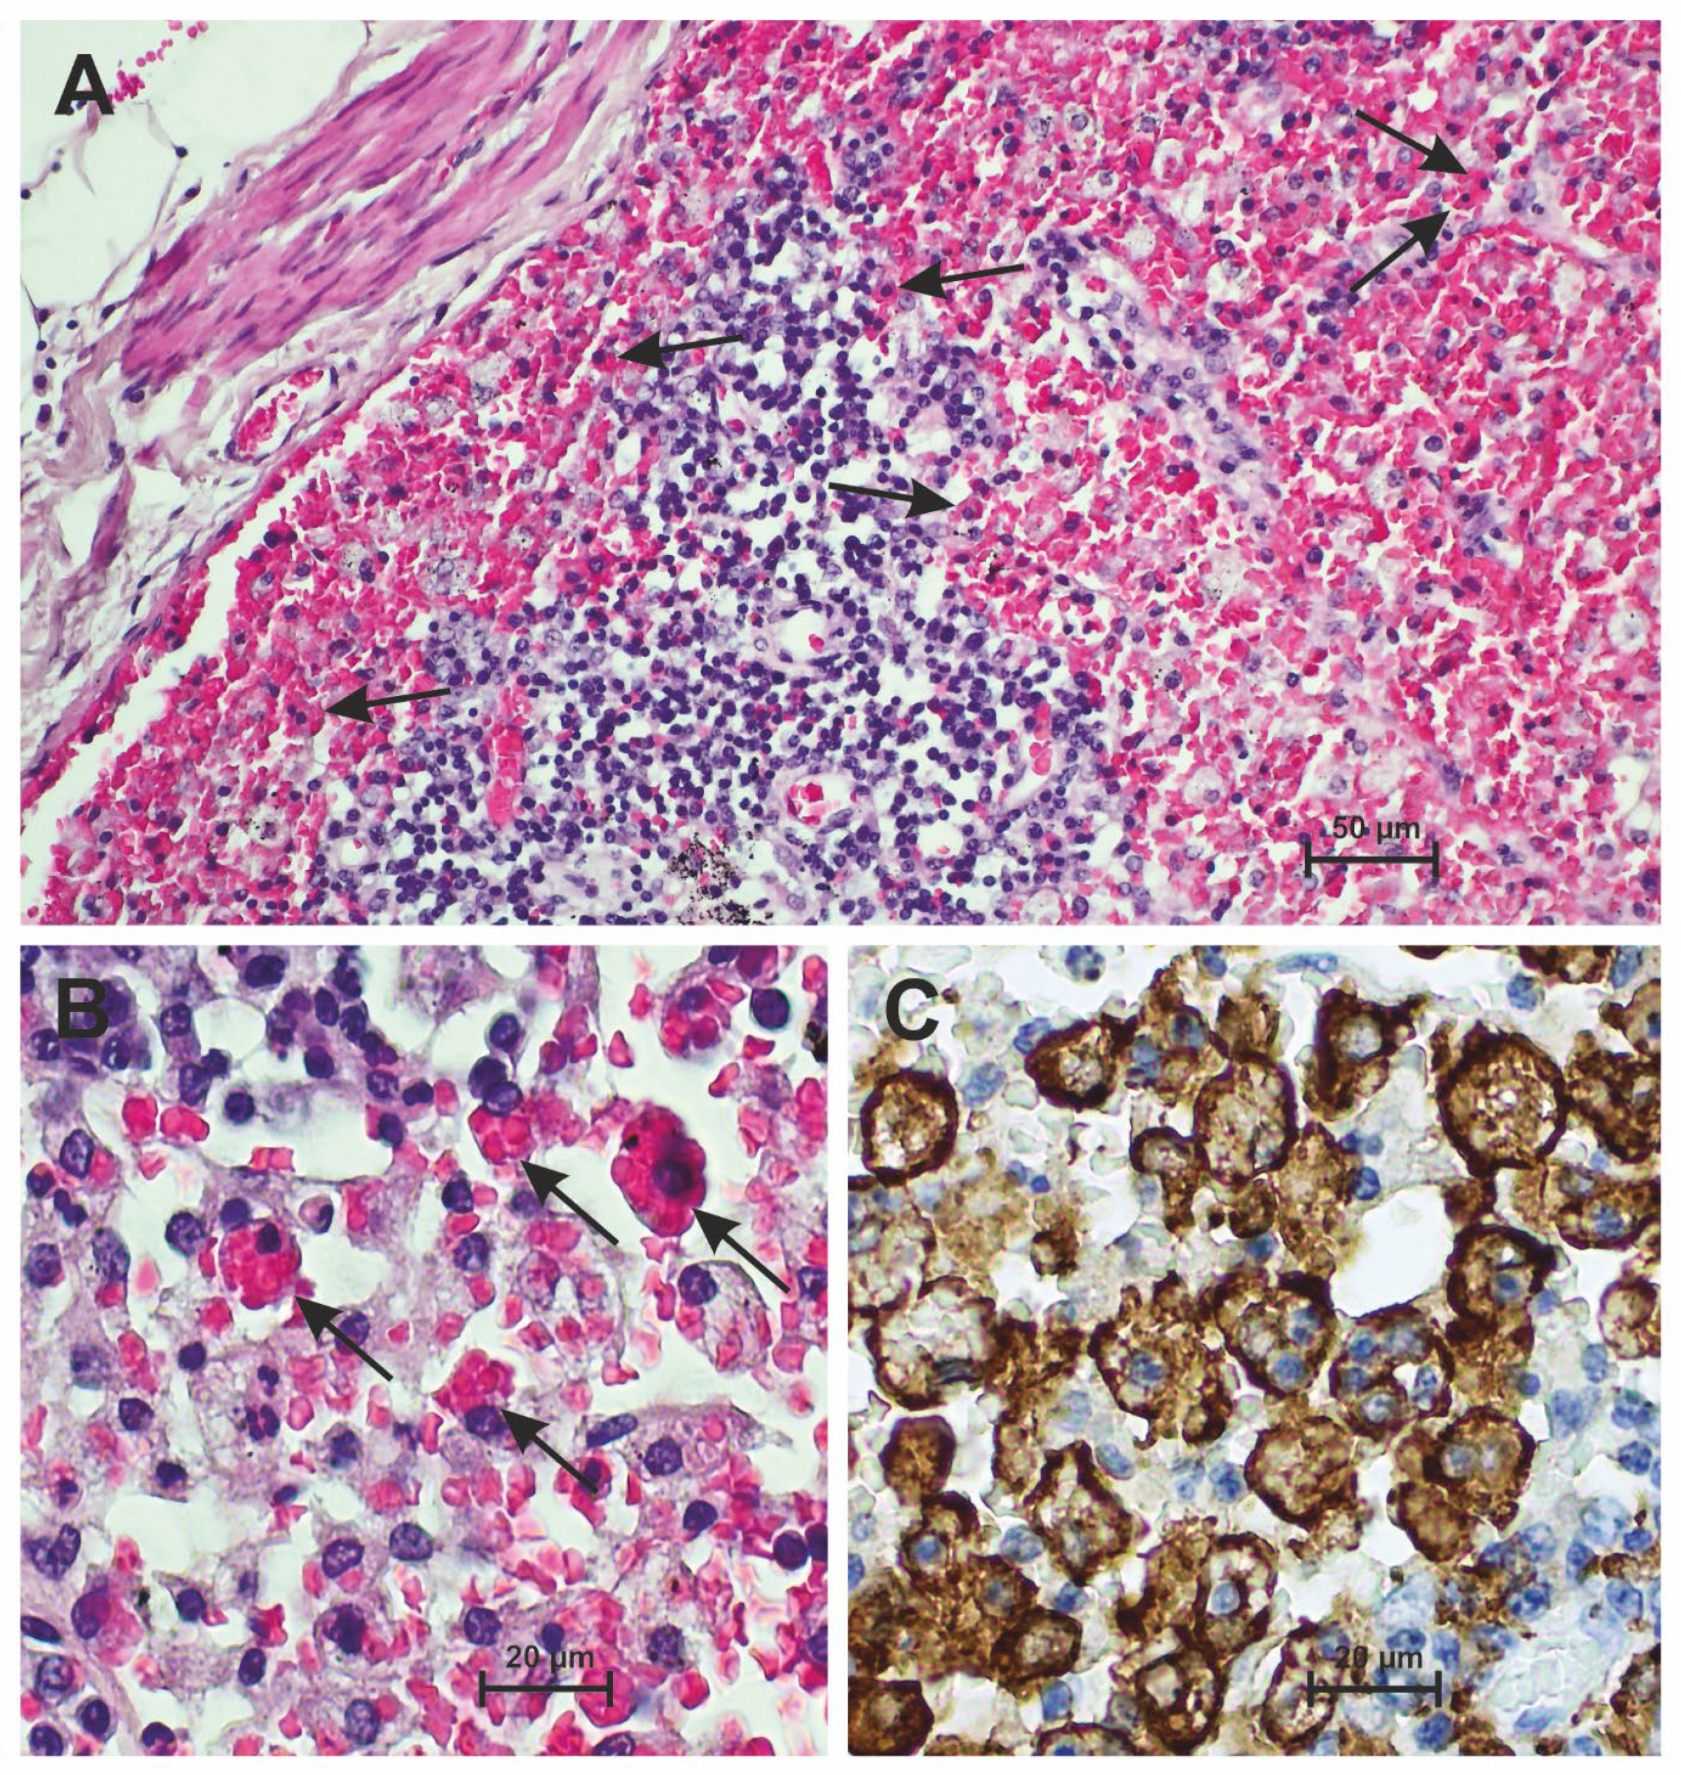

3.2. Hemophagocytosis Is Found in the Lymph Nodes of Patients Who Have Died from Severe COVID-19

3.3. Hemophagocytosis Is Found in the Bone Marrow of Patients Who Have Died from Severe COVID-19